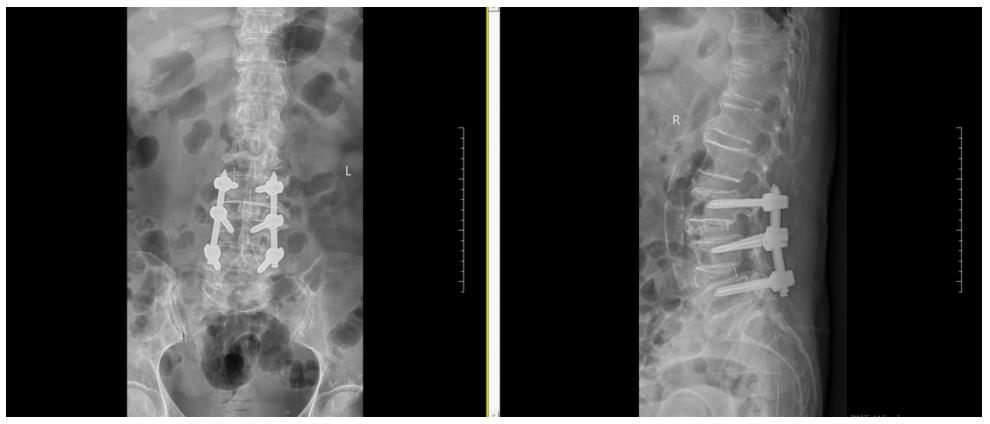

▲患者术前影像学资料

女性患者陈大妈61岁,因“腰痛伴双下肢麻痛5年。”入院。曾辗转区内外多家医院求医,诊断为“1、腰椎管狭窄症;2、腰椎滑脱症”,经过反复保守治疗,但是效果不佳,严重影响日常生活。我院脊柱微创科王义生主任专家团队通过会诊,一致认为可进行手术治疗。本着“微创化”的治疗理念,结合患者实际需求,制定了详细有效的手术治疗方案。在与患者及家属充分沟通后,决定为患者实施OSE (Open Spinal Endoscopy, Openscopy)-单孔双入路脊柱内镜(开放式脊柱内镜,分体式脊柱内镜)术。